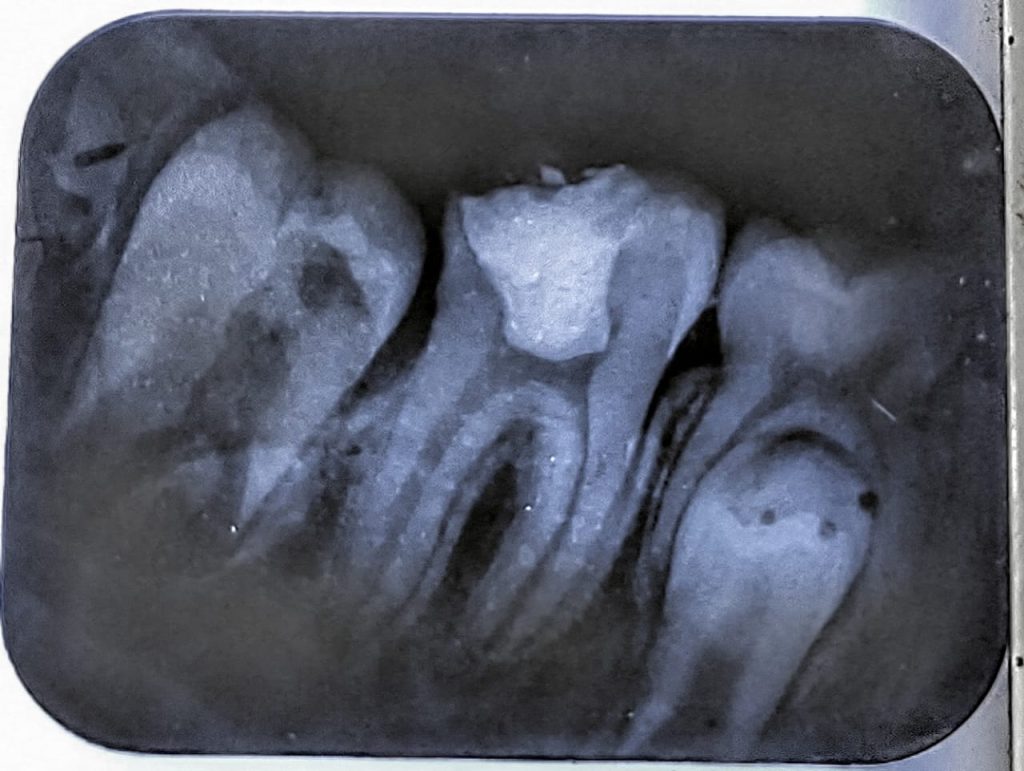

Formacresol pulpotomy till cervical constriction followed by placing calcium hydroxide as pulp capping agent for apex formation to occur naturally. sealed the tooth with temporary restoration and put the patient on 6 months follow up.

after 6 months, the tooth shows visible apical constrictions and patient had no pain. redone the temporary restoration and again put patient on 6 months follow up for complete apex formation.